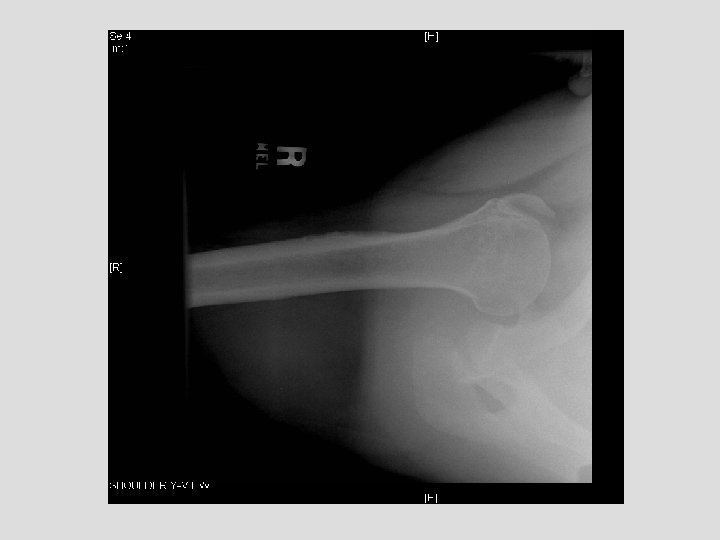

Findings and Differentials Findings: On the CXR, there is a piece of bone overlying

Findings and Differentials Findings: On the CXR, there is a piece of bone overlying the right scapula, which could easily be missed. The follow-up shoulder series and CT more clearly demonstrate a fracture. The CT clearly shows the donor site to be the coracoid process. Differentials: • Coracoid avulsion fracture